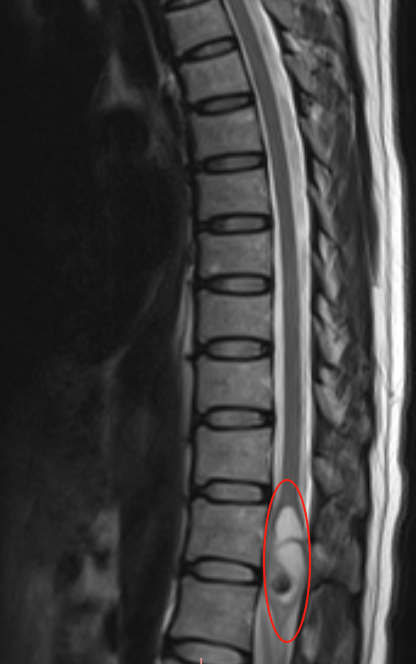

术前MRI检查报告

持续两年的反复腰痛,起初她并未特别在意。直至今年八月一次飞行途中,飞机遭遇气流出现颠簸,剧烈震动导致其腰痛突然发作,此次再也无法忽视。后续MRI检查发现T12水平存在髓内占位。她前往多地求医,征询多位医生意见,得到不同说法:有的医生肯定地表示手术没有问题,也有医生对手术风险描述令人担忧。

为何该手术难度较高?从解剖学角度看,该部位结构极为复杂,脊髓于此终止,并延续为所谓的终丝。此处发出大量神经根,前方为运动神经,后方负责感觉,解剖形态呈马尾状。肿瘤部分位于脊髓圆锥内,部分与这些神经有轻微粘连,同时伴有血管分布,因此情况较为复杂。术中若牵拉不当或双极电凝止血过度,可能引起脊髓梗塞,导致瘫痪、意识障碍、大小便功能障碍等严重并发症。